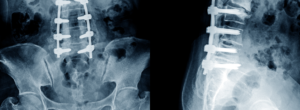

4- Estenose espinhal

A estenose espinhal é um estreitamento do canal espinhal, que pode comprimir a medula espinhal e os nervos, resultando em dor, fraqueza e dormência.

5- Espondilolistese

A espondilolistese ocorre quando uma vértebra se desloca sobre a outra, causando dor e, possivelmente, compressão dos nervos.